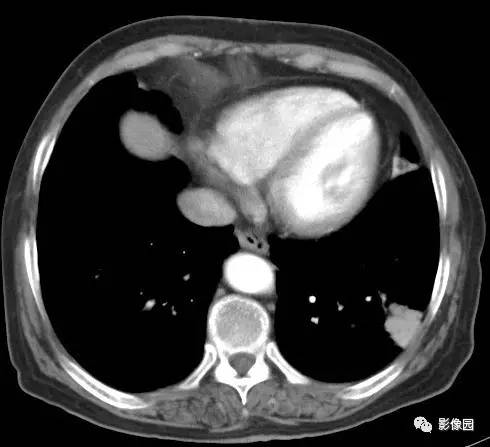

左下肺鳞癌1例CT

病史:女,77,体检发现左下肺占位5天。CT平扫肿物CT值约为40Hu,增强后约95HU

穿刺结果:(左下肺)部分肺组织:慢性支气管炎及支气管周围炎,肺泡间质纤维组织增生,个别支气管粘膜鳞状上皮化生,部分恶变,呈鳞状上皮原位癌结构,极个别区域有支气管壁早期浸润。